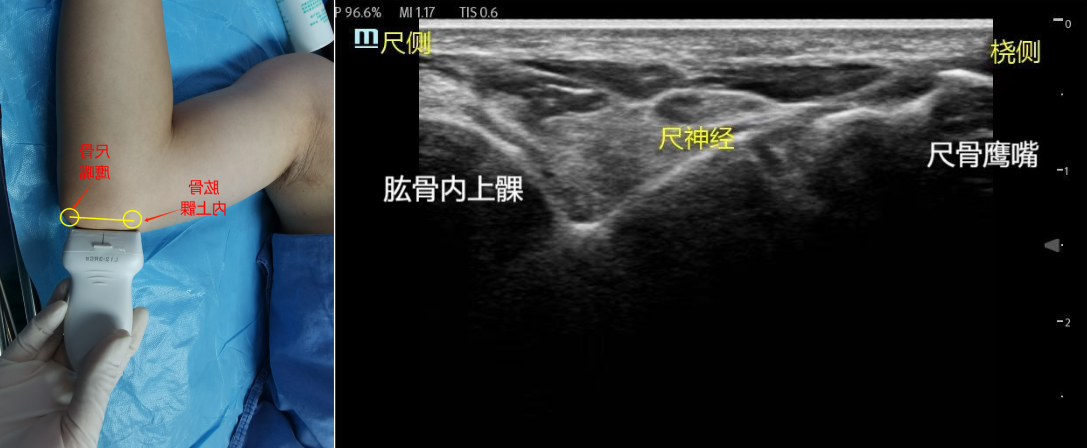

1、肘关节入路:解剖关键点:肘关节处肱骨的内上髁、尺骨的鹰嘴、肱动脉。体位:为平卧位,手臂外展90°。步骤:探头放在肱骨内上髁与尺骨鹰嘴之间,或偏远端(前臂端,该处皮下组织多,图像显示好),即尺神经沟处,探头与肱骨垂直。类圆形的筛网状为尺神经。平面内法或平面外法,药物注射在神经周围。注意因该处组织致密,该处注射药物时,药量不宜过大,以免压迫尺神经而受到损伤。药物用量:0.25%-0.5%罗哌卡因1-2ml。